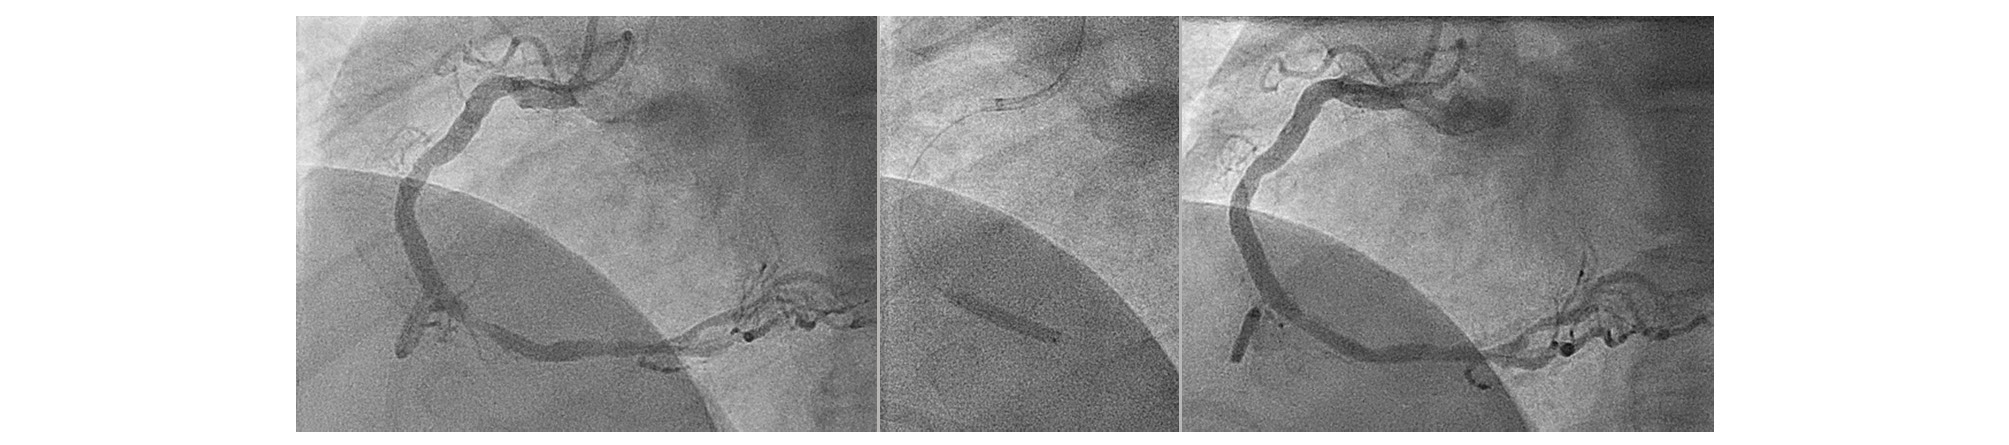

Figure 1. Thrombotic lesion in a right coronary artery in a patient after out-of-hospital cardiac arrest (OOHCA) and resuscitation. Lesion preparation with a scoring balloon followed by a 3.5x20 mm paclitaxel-coated balloon.

Drug-coated balloon (DCB)-only angioplasty is a rapidly expanding area of both clinical interest and research in the field of coronary intervention. Randomised clinical trials (RCTs) and registries have shown the non-inferiority of DCB-only percutaneous coronary intervention (PCI), as compared with routine, standard-of-care drug-eluting stent (DES) implantation, in a number of clinical settings and lesion types. However, the most high-risk and possibly most complex angioplasty that is often done is in the setting of an acute coronary syndrome (ACS), particularly ST-elevation myocardial infarction (STEMI) primary PCI (PPCI) or out-of-hospital cardiac arrest (OOHCA) (Figure 1). There are limited data available for the use of DCBs in the setting of an ACS; we will review this along with the potential advantages and disadvantages of adopting a DCB approach.